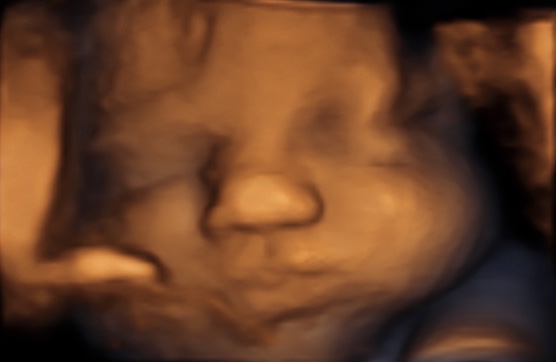

30 weken

Een echo na 30 weken.